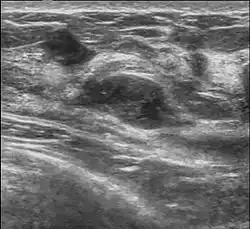

L'adénofibrome (ou fibroadénome) est une tumeur bénigne du sein composée de tissus fibreux et de tissus glandulaires atteignant la glande mammaire. Cette tumeur bénigne est la plus fréquente des tumeurs solides du sein. Elle survient essentiellement chez les jeunes femmes, souvent avant 30 ans, mais peut apparaître à tout âge[1].

L'adénofibrome du sein se caractérise par une consistance solide, ferme et bien limitée. Il se distingue d'autres tumeurs par sa forte mobilité. Ils mesurent généralement entre 2 et 3 cm de diamètre ; et peuvent être solitaires ou multiples, unilatéraux ou bilatéraux.

L'adénofibrome peut être perçu par la femme elle-même par la palpation des seins (perception d'une petite boule au niveau du sein, unique et indolore) ou lors d'une consultation chez sa gynécologue mais l'examen clinique, l'exploration radiologique par la mammographie et l'échographie permettent de confirmer le diagnostic ; dans certains cas, l'analyse d'un prélèvement par cytoponction (prélèvement d'un échantillon de la tumeur par une ponction à l'aide d'une aiguille spécifique) ou, plus récemment, par microbiopsie, est nécessaire pour s'assurer de la nature bénigne de la tumeur.